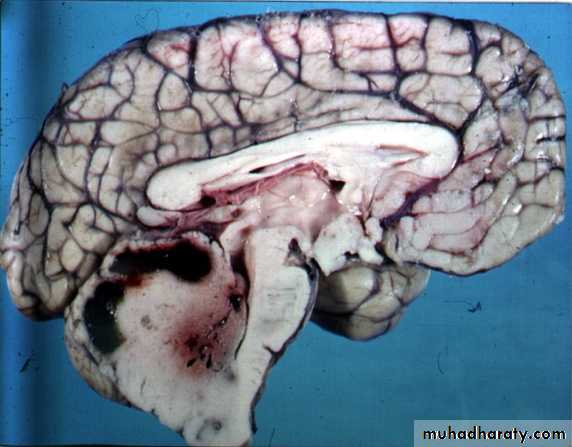

Glioblastoma multiformis:

The most malignant brain tumor, rapidly growing , red in color, highly vascular mainly affecting the cerebrum , some pathologists classify it as astrocytoma grade IV.Medulloblastoma:

Tumor of childhood, affecting the posterior fossa, usually a midline tumor & highly malignant.